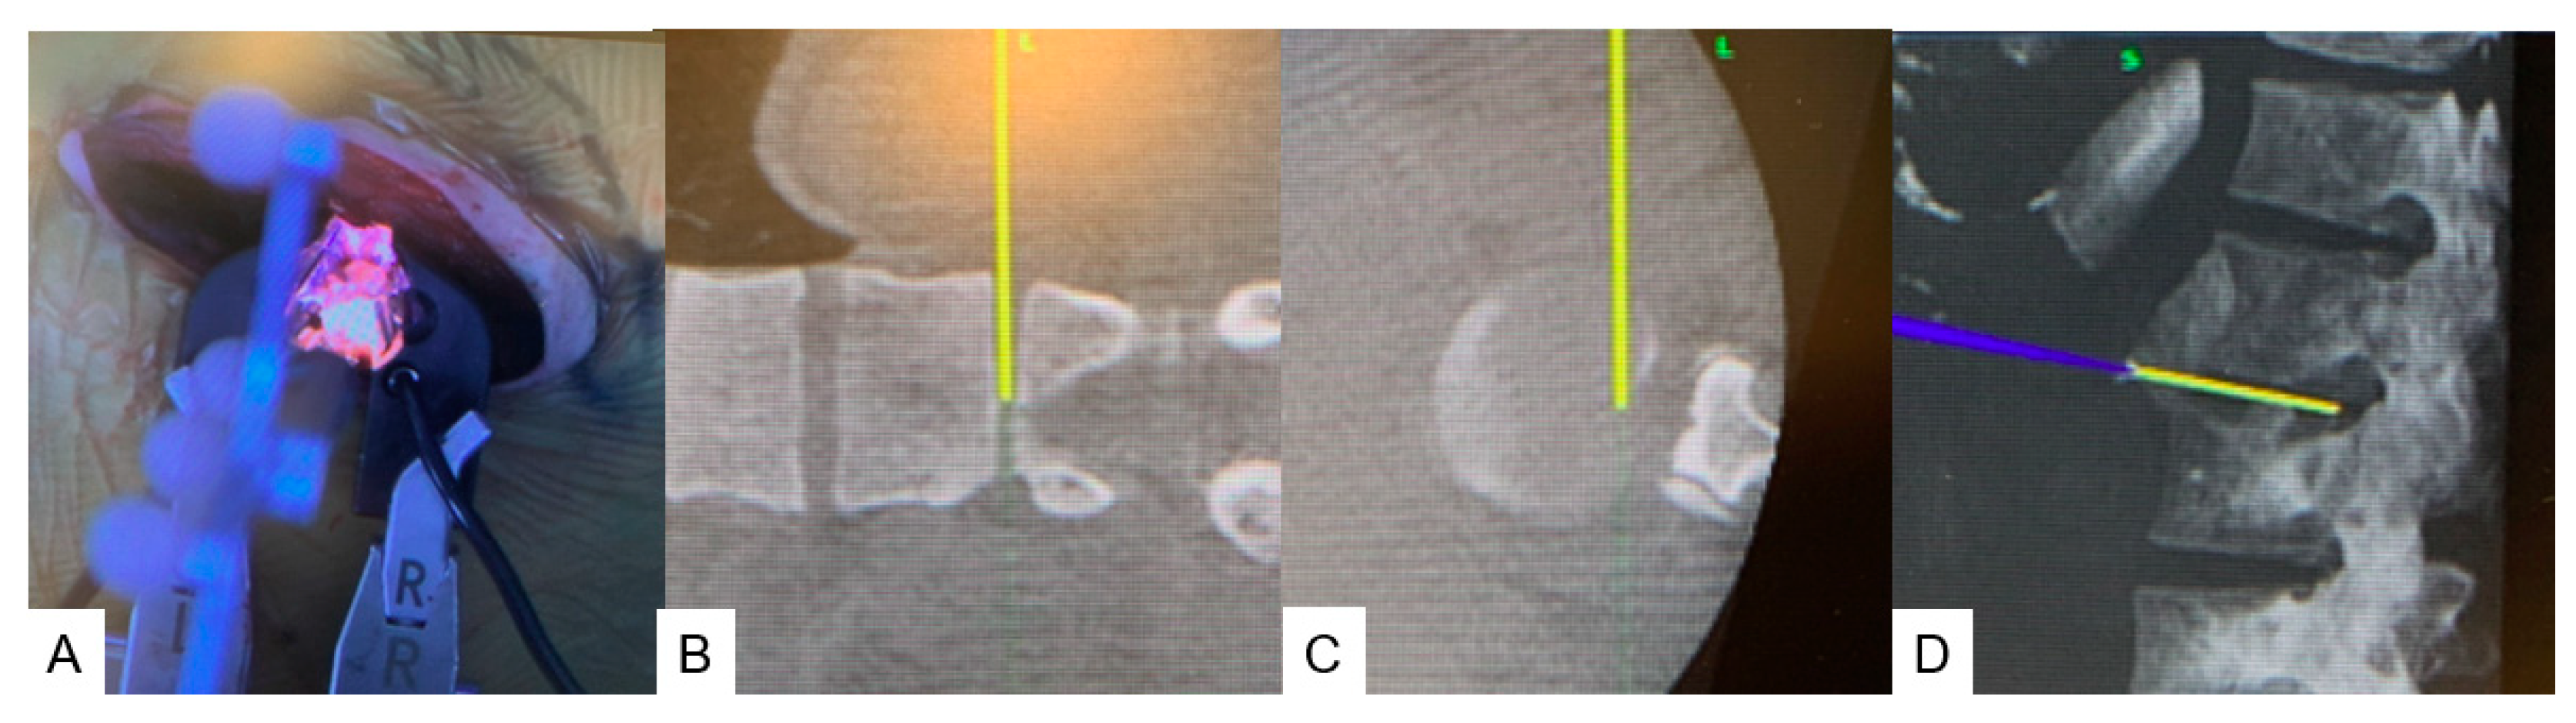

2.4.1. Anterior Discectomy

2.4.2. Posterior Osteotomy